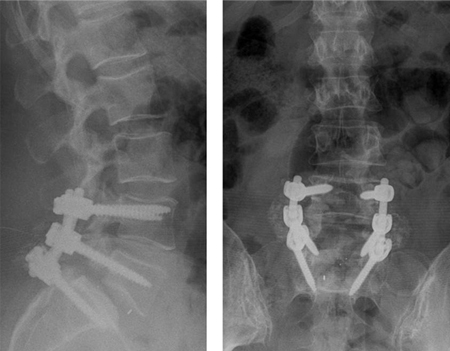

[Figure caption and citation for the preceding image starts]: Postoperative radiographsFrom the collection of Dr N. Quiraishi [Citation ends].

[Figure caption and citation for the preceding image starts]: Pre- and post-surgical views: a patient presents with back pain and neurogenic claudication with stenosis and degenerative slip at L4-5 and a degenerate disc at L5S1 (left, T2-weighted sagittal MRI); L4-S1 decompression and instrumented fusion and a 2-level transforaminal lumbar interbody fusion was performed (AP radiograph top; lateral, bottom)From the collection of Dr N. Quiraishi [Citation ends].